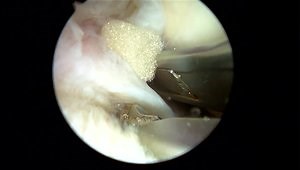

All-inside undersurface meniscal tear repair

Meniscal Repair

All-Inside Longitudinal Meniscal Repair

Meniscal Repair Techniques

Meniscal Repair - Surgery Demo

All-Inside Meniscal Repair Utilizing a Flexible Needle

All-inside Non-capsular Fixating Chronic Complex Lateral Menisca

Meniscal Repair Techniques a 2023 Update

All-inside meniscus repair

Inside Out Meniscus Repair

Mastering the Meniscus: Five Meniscal Tear Types Repaired

All-Inside lateral meniscus radial tear repair

All-Inside Repair of Radial Medial Meniscus Tear

All Inside Meniscus Repair with FAST-FIX™ 360

Lateral Meniscus Repair - Inside Out Technique

Meniscus Root Repair and Inside-Out Repair Techniques

Meniscus Flap Root Tear | Full Repair with All Suture Technique

Arthroscopic Meniscus Repair Using the SuperBall™ All-Inside,

Meniscus Repair Techniques

Medial Meniscus Root Repair with All-Suture Anchor

Meniscus Pathology: Repair, Rehabilitation and Results

Knee All inside Meniscal Repair

Meniscus Flap + Root Tear | Full Repair with All Suture Techniques

Advanced All-Inside Meniscus Repair Technique Explained

Meniscus Repair Surgery